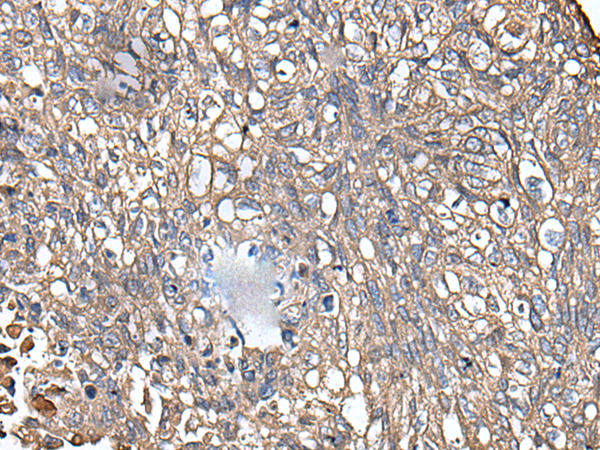

Keratins are intermediate filament proteins responsible for the structural integrity of epithelial cells and are subdivided into epithelial keratins and hair keratins. This gene encodes a protein that is expressed in the inner root sheath of hair follicles. The type II keratins are clustered in a region of chromosome 12q13. |

ELISA, IHC |

IHC positive control: |

Human prostate cancer and human lung cancer |

IHC Recommend dilution: |

40-200 |